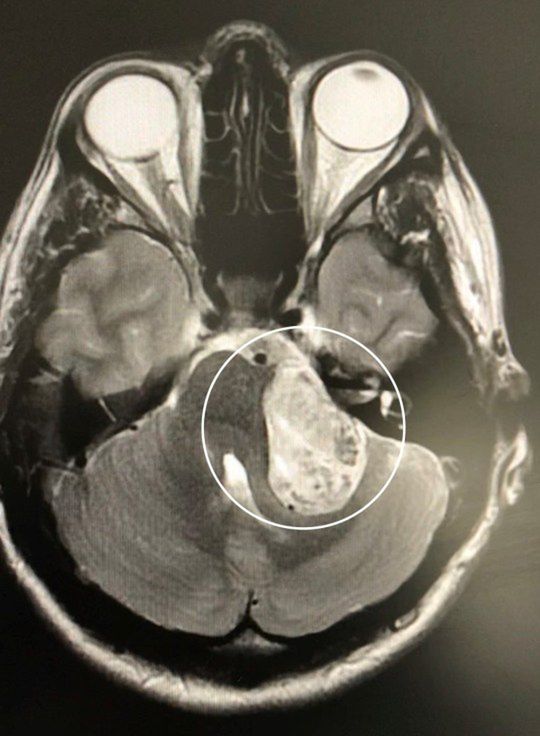

Podczas biegania kobieta straciła równowagę i uderzyła o ścianę ogrodu. Upadek skłonił ją do wykonania rezonansu magnetycznego. Wyniki MR pokazały, że problemy nie są spowodowane zaburzeniami natury psychicznej, lecz guzem mózgu wielkości piłki golfowej.

Kiedy badanie ostatecznie wykazało obecność guza w jej mózgu, zdiagnozowano go jako nerwiaka słuchu - łagodnego guza, który według organizacji charytatywnej British Acoustic Neuroma Association (BANA) dotyka około 2 na 100 000 osób w Wielkiej Brytanii rocznie.

Lekarze stwierdzili, że guz mózgu uciskał nerwy kontrolujące słuch i równowagę i był odpowiedzialny za objawy uznane wcześniej za te charakteryzujące zaburzenia lękowe.